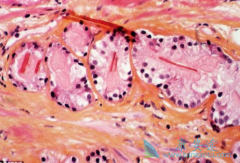

胆囊癌 (Gallbladder cancer, GBC)是指发生于胆囊(包括胆囊底部、体部、颈部以及胆囊管)的恶性肿瘤,其发病具有典型的地域性、种族和性别差异性。胆囊癌的发病率(我国)占同期胆道疾病的0.4%-3.8%,相对罕见,但其早期症状隐匿,生物学行为恶劣, ...